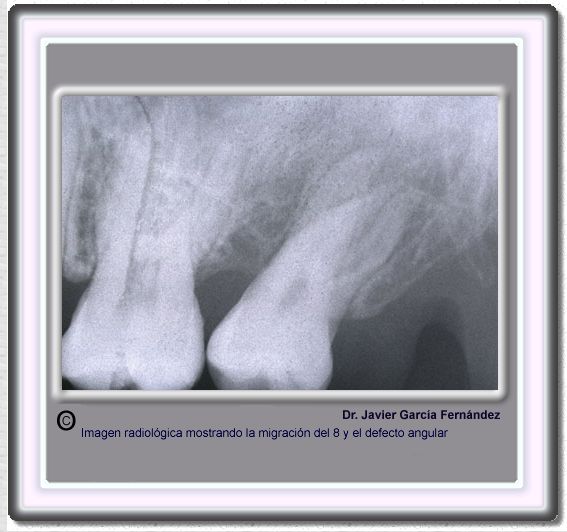

image434